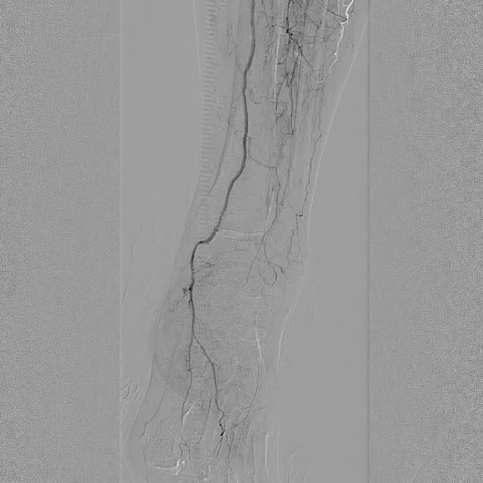

选用2×40mm普通球囊扩张闭塞病变,造影可见局部内膜撕裂严重,形成明显夹层(提示病变坚硬,需支架支撑)。

造影显示:胫腓干动脉血流恢复通畅,支架形态及位置理想,胫后动脉显影较术前明显改善;

腔内超声证实:铁支架完全张开、贴壁良好,无明显残余狭窄。